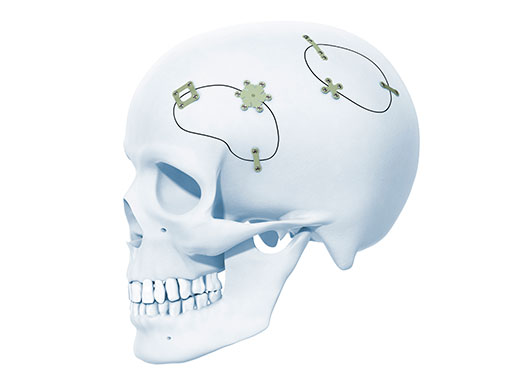

The new MatrixNeuro Ultra Low Profile (ULP) system (Fig 1) was developed in response to the need to decrease implant profile whilst also providing comparable construct stiffness and strength to the plates in the existing MatrixNeuro system.

The plate thickness is only 0.28 mm (MatrixNeuro standard plates are 0.40 mm). Also, the screw recess was improved (Fig 2) to achieve a better seating of the screw, which has led to a plate-screw profile of 0.44 mm, a reduction of another 10% compared with the existing system. And instead of having a rectangular edge, the plates are chamfered to achieve almost no palpability under the skin (Fig 3).

A wide range of plates is available (Fig 4) based on the most frequently used MatrixNeuro standard plates, ie, Burr Hole Covers ranging from 1224 mm with one additional version for shunt or drainage, as well as straight plates with center space in 2-hole and 4-hole versions. The system is completed with an X Plate, a square and a rectangular Frame Plate, a Double Y Plate, and a Strut Plate.